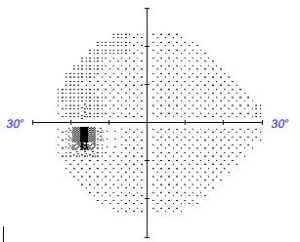

Consider the 2 physiological blind spots in our vision. It is due to the lack of photoreceptors at the optic nerve. Yet we do not notice these areas of missing vision.

It is thought that the brain “Fills in” the defect.

The brain perceptually bridges gaps by interpolating surround features and thus restores a retinal image that is incomplete.

It may also be doing the same for incomplete images due to retinal, optic nerve or central nervous system conditions.

However, if the stimulus is inherently dynamic and unpredictable. the “Fill in” is imperfect.

The viewer with the incomplete image now perceives the hampered attempt at “Fill in” as the dark area that it ought to be. The viewer in fact sees their visual field defects for maybe the first time.